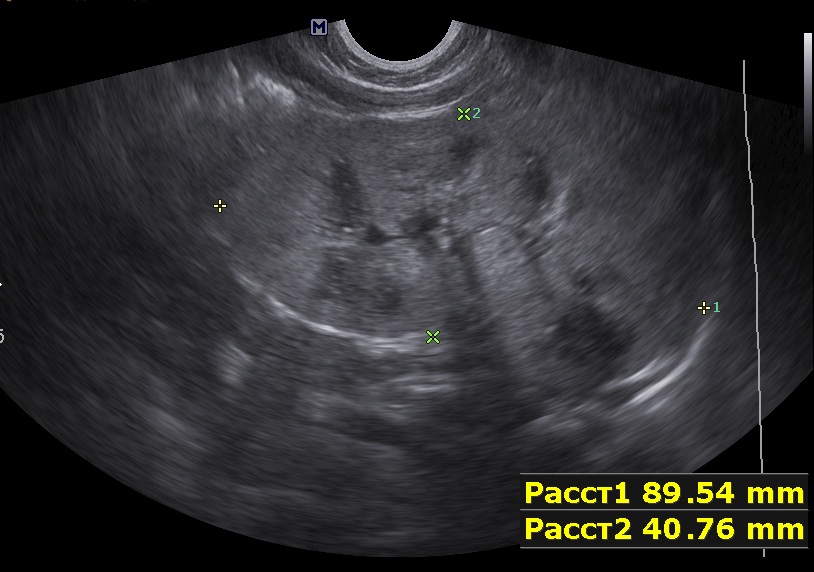

Ребенок 9мес, старшая сестра 9лет с ювенильным поликистозом (в н.в. ХБП 2).

Первые изменения в 1 мес, увеличение размеров почек.

Осмотрен мной ребенок впервые, обращено внимание на большие почки, 90х40мм, паренхима 17-18мм, корковый слой гиперэхогенный, пирамидки дифференцируются. Линейным датчиком определяется: кисты или расширенные канальцы в пирамидках. Структура печени в 1 мес была не изменена, в н.в. отмечается перипортальный фиброз, размеры печени и селезенки увеличены.

Поставил медуллярную кистозную дисплазию, почитав литературу предполагаю нефронофтиз Фанкони, но к сожалению не нашел картинки только описание данной болезни. Поделитесь своим мнением.

левая почка.jpg